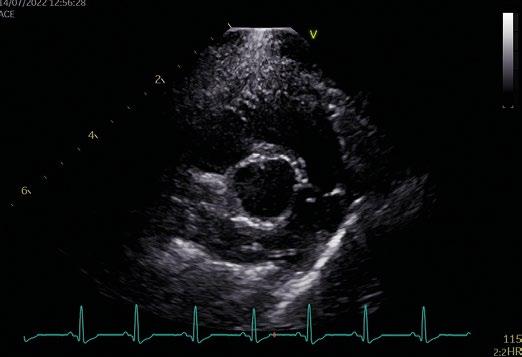

Utilidad clínica de la ecografía pulmonar y cardiaca en urgencias